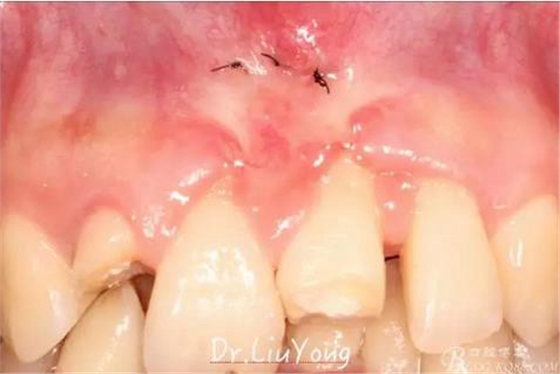

上唇系帶手術(shù)后一周拆線,如上圖